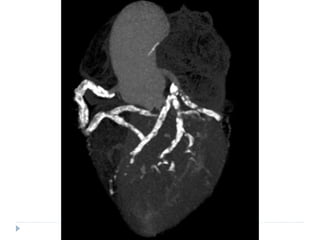

Blood supply to kidney - nephrons

Normal circulation Renal circulation

The renal circulation is unique

• It has two capillary beds, the glomerular and peritubular

capillaries, which are separated by the efferent arterioles, which

help regulate the hydrostatic pressure in both sets of capillaries.

• High hydrostatic pressure in the glomerular capillaries (about 60

mm Hg) causes rapid fluid filtration

• Lower hydrostatic pressure in the peritubular capillaries (about

20 mm Hg) permits rapid fluid reabsorption.

• By adjusting the resistance of the afferent and efferent

arterioles, the kidneys can regulate the hydrostatic pressure in

both the glomerular and the peritubular capillaries